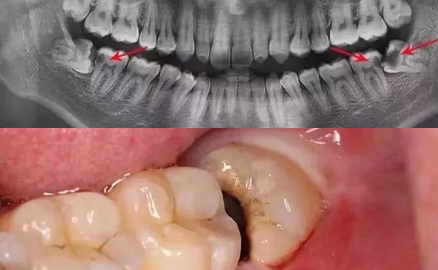

智齒周圍食物阻塞 不易清潔 造成大臼齒後方深部蛀牙 利用樹脂全瓷嵌體修復 牙科美容資訊 美容牙科張凱榮醫師